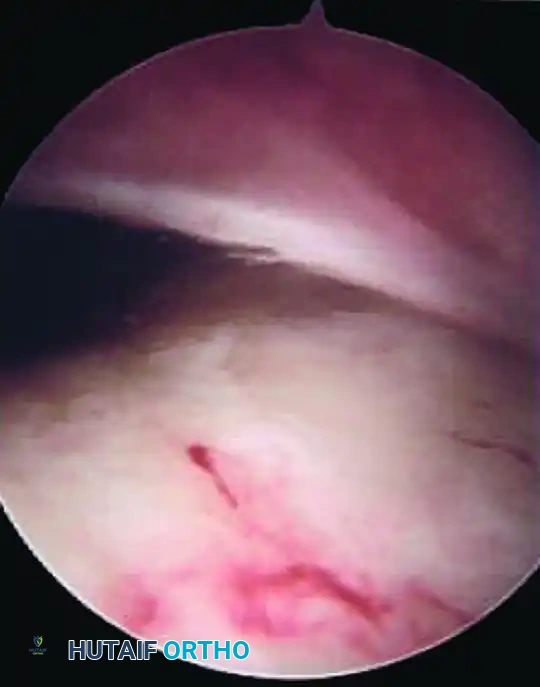

ARTHROSCOPIC DIAGNOSIS

Despite advances in non-invasive imaging, an abnormal plica is diagnosed best by direct arthroscopic examination of the knee. Arthroscopy serves as both the definitive diagnostic gold standard and the primary therapeutic intervention.

Image

During diagnostic arthroscopy, careful assessment of the width, thickness, and texture of the plica by viewing and tactile probing is paramount. A normal plica will feel soft and yield easily to the probe. A pathological plica will feel rigid, fibrotic, and unyielding.

Surgical Warning: When a suprapatellar or medial plica is sufficiently prominent, it can present significant difficulties during the initial stages of arthroscopy. The plica may act as a physical barrier as the arthroscope is introduced into the suprapatellar pouch, potentially leading to iatrogenic scuffing of the trochlear cartilage if forced.

Furthermore, the surgeon must dynamically evaluate the plica. By viewing from the anterolateral portal and slowly flexing and extending the knee, the surgeon can directly observe the medial plica impinging upon and abrading the medial femoral condyle, confirming its pathological nature.